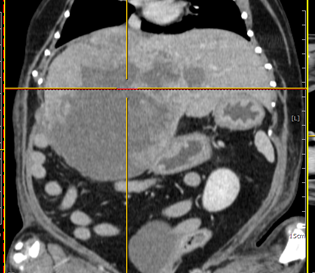

CT촬영을 통한 PSS 질환 진단